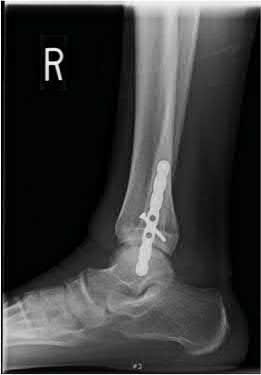

A 25-year-old male sustains an ankle fracture dislocation and undergoes open reduction and internal fixation. He returns to clinic five months following surgery complaining of continued ankle pain and instability with weight bearing. His immediate post-operative AP radiograph is seen in Figure A. Which of the following could have prevented this patient from developing persistent pain?

The patient presents with continued ankle pain and instability following open reduction and internal fixation. The radiograph in figure A demonstrates inadequate restoration of fibular length, likely leading to continued tibiotalar instability.